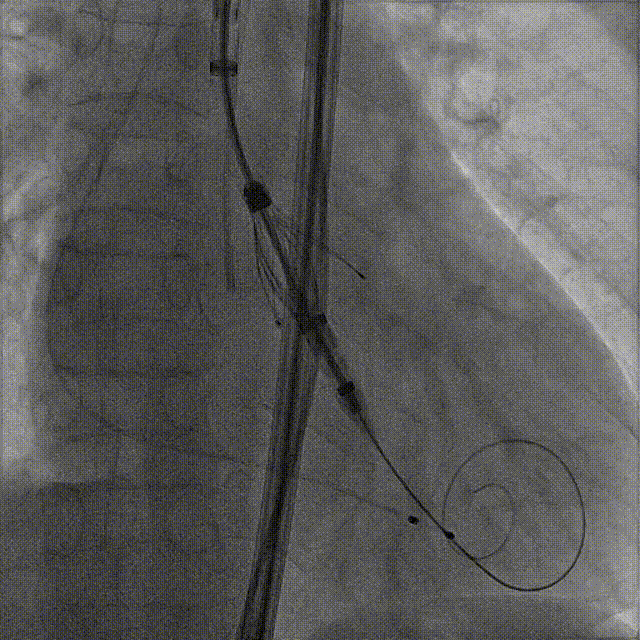

Case 3

瓣上风湿性粘连伴有狭窄重度反流

术前CT评估

根据瓣环与 LVOT-6 mm 平面,备后扩解决瓣上,避免瓣周漏,选择:M 号 TaurusTrio

手术过程:5A 标准化流程SOP

术前右窦中心造影

大鞘植入

瓣膜调弯解离

定位键窦对齐验证

定位键入窦验证

深度检查

一键释放

后扩后造影